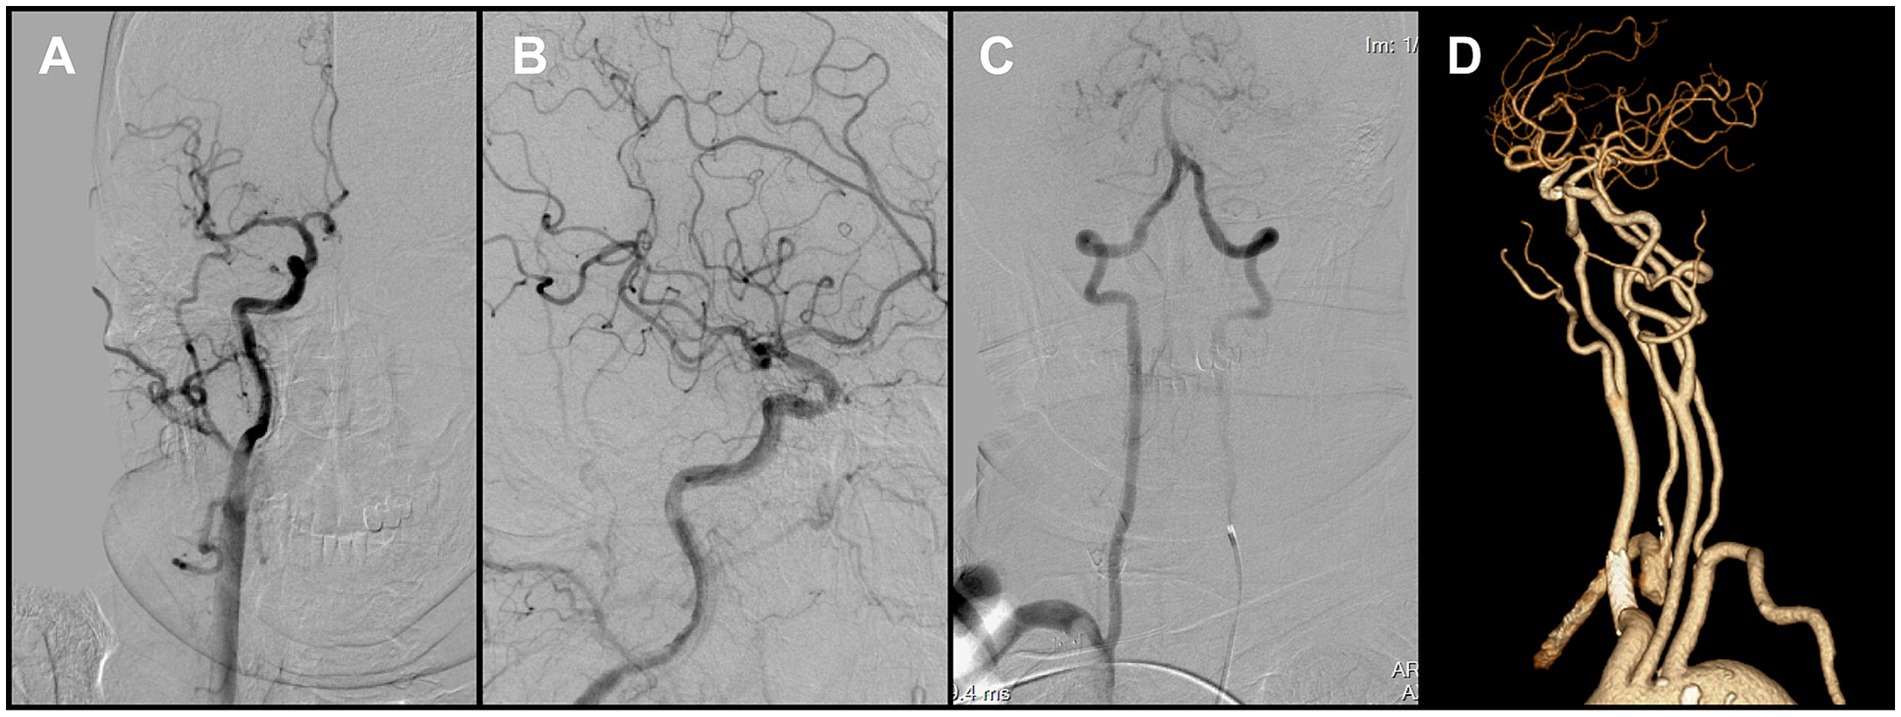

The Neuron MAX catheter was then advanced into the distal right CCA near the bifurcation. Before performing a complete diagnostic angiogram, a contrast injection was used to confirm catheter position. At this point, a large FFT was identified at the carotid bifurcation, involving into the origins of both the ICA and the ECA. The thrombus exhibited pulsatile motion synchronous with the cardiac cycle, consistent with a mobile/mural thrombus (Figure 2A). At the same time, antegrade flow in the ICA was stagnant, suggesting distal ICA occlusion. The overall presentation was therefore consistent with a tandem embolic lesion in the anterior circulation. Given the presence of collateral circulation, a proximal-to-distal treatment strategy was adopted.

Figure 2. (A) Right carotid angiography revealed a free-floating thrombus at the carotid bifurcation. (B) Following removal of the proximal thrombus, angiography showed persistent non-opacification of the distal right internal carotid artery (ICA). (C) Contrast injection after crossing of the occluded segment by the microcatheter delineated the distal vessel. (D) Post-stent deployment angiography demonstrated absence of antegrade flow across the occluded segment.

Aspiration thrombectomy was attempted through the Neuron MAX catheter, but resistance was encountered, suggesting catheter-tip or intraluminal clot occlusion. Continuous and pulsed aspiration failed to restore flow, and blind catheter withdrawal was avoided due to the risk of embolic escape. Therefore, a Solitaire 4 × 20 mm stent retriever (Medtronic, USA) was deployed at the tip of the Neuron MAX guiding catheter. With continuous aspiration applied through the guiding catheter, the stent was used to scrape and engage the obstructing thrombus. This maneuver was repeated three times, after which the guiding catheter was successfully cleared and patency restored. Subsequent angiography demonstrated complete removal of the thrombus at the bifurcation of the right internal carotid artery (Figure 2B).

2.3 Intracranial flow restoration and proximal lesion

After restoration of catheter patency, the Neuron MAX catheter was navigated into the ICA. A Catalyst 6 aspiration catheter (Stryker Neurovascular, USA) was advanced and used to aspirate thrombotic material from segments C1 through C4 of the right ICA, with adequate backflow but no significant thrombus was retrieved. The microcatheter and microwire were then used to traverse the terminal ICA occlusion and advance into the distal M1 segment (Figure 2C). Following deployment of the Solitaire stent retriever, angiography still showed no antegrade flow (Figure 2D). Because of the heavy thrombus burden, a combined approach was adopted, retrieving the stent retriever together with en bloc withdrawal of the aspiration catheter.

During this phase, impaired backflow in the Neuron MAX catheter was observed. After the catheter was withdrawn to the common carotid artery, adequate backflow through the guiding catheter was restored. Catheter angiography demonstrated severe vasospasm of the right ICA, explaining the earlier loss of backflow. In addition, a small residual thrombus was detected in the distal M1 segment (Figure 3A), and a previously unrecognized thrombus was identified in the right CCA (Figure 3B). After discussion, the team decided to prioritize treatment of the intracranial lesion. However, when the catheter was advanced into the ICA for follow-up angiography, the residual thrombus was found to have migrated spontaneously into an M4 cortical branch, and the ICA vasospasm had also resolved spontaneously. At that point, intracranial reperfusion was satisfactory, with an mTICI score of 2b, and no further treatment was required.

Figure 3. (A) Right common carotid angiography showed a small residual thrombus at the distal right middle cerebral artery (MCA) that did not significantly compromise hemodynamics. (B) A large thrombus was identified in the right common carotid artery, adjacent to the delivery catheter. (C) Brachiocephalic angiography with distal protection demonstrated a large free-floating thrombus (FFT) involving the brachiocephalic bifurcation, extending into the origins of the right common carotid and right subclavian arteries. (D) Post-stenting angiography demonstrated full expansion of the stent in the right common carotid artery (CCA), without residual stenosis at the treatment site.